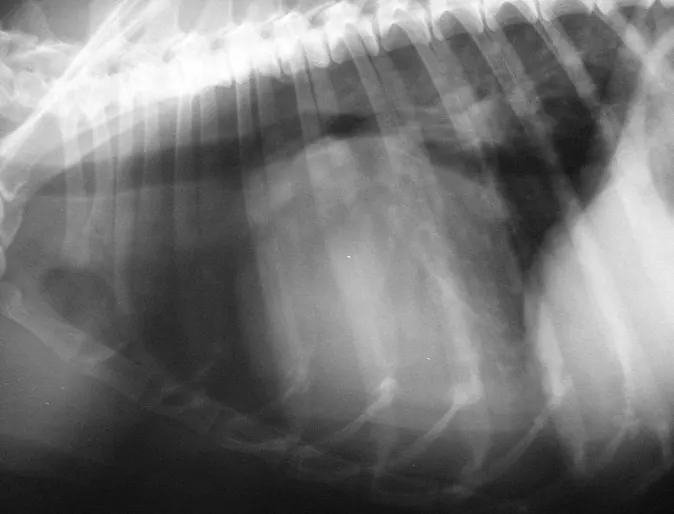

The Monster Hairball

Murphy is a 10 year old male Himalayan cat who presented to us with a history of not eating for a few days. He was also vomiting and the owners noticed blood in the vomit at times. Murphy was admitted for bloodwork and abdominal radiographs (x-rays) to try and track down the cause of his illness.